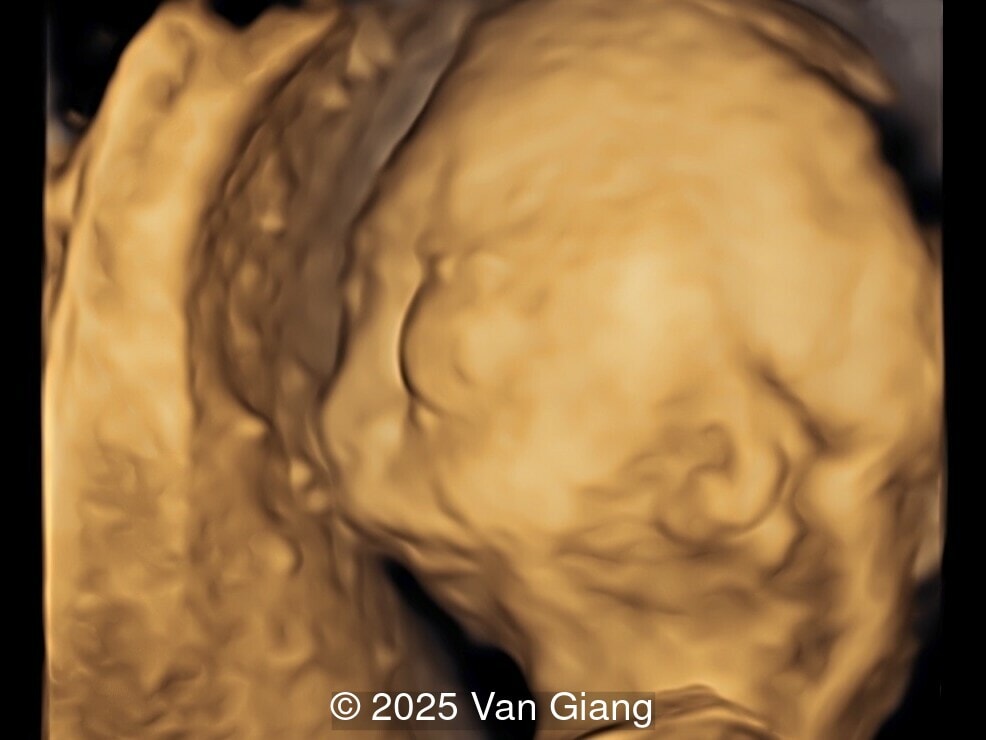

A 32-year-old primigravida presents at 20 weeks gestation without first trimester screening. Ultrasound reveals a small for gestational age fetus with the following anomalies:

fetal profile

Image 1 fetal profile

Ultrasound revealed severe mandibular and zygomatic hypoplasia, glossoptosis, cleft palate, and micrognathia with an abnormal facial profile. Both upper limbs showed radial ray sequence with abnormal thumbs and shortened forearms. Unilateral clubfoot was also noted. No major cardiac or visceral anomalies were observed. Based on these findings, Nager syndrome was suspected.